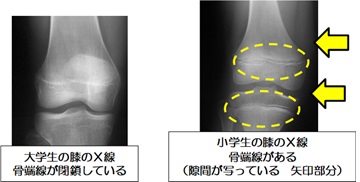

身長は、骨の両端にある硬い部分と柔らかい部分の境目(骨端線)がHSPとGHの働きにより成長することで伸ばすことができます。

骨端線は剥がれやすいため、ラグビー前の準備運動を十分に行なうことが重要です。

※骨端線がはがれるを剥離骨折といいます。